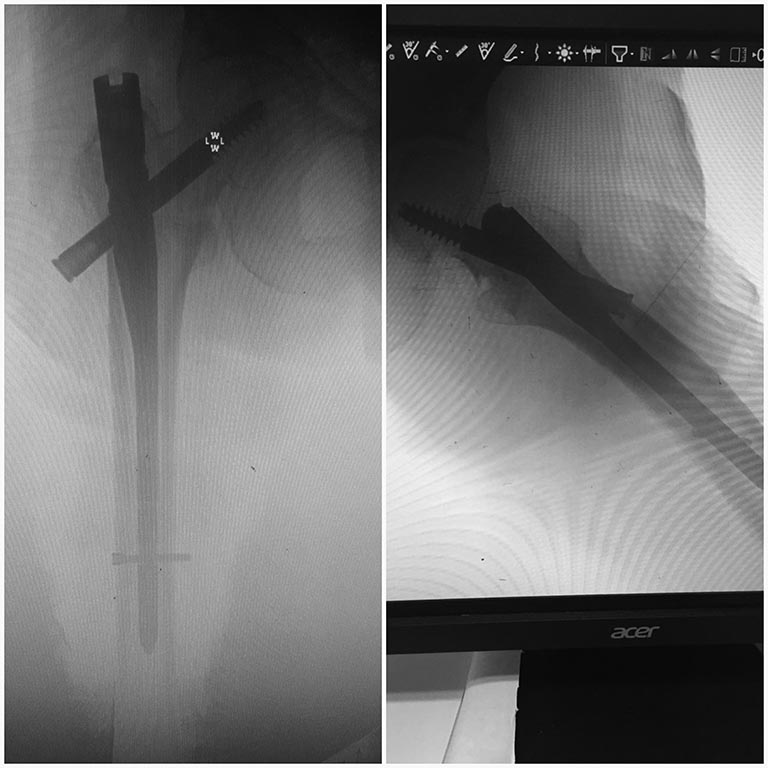

При установке Y-гвоздя возник вопрос, существует понятие допустимое выстояние шеечного винта в см. относительно диафиза бедра?

Когда его можно оставить(торчит),а когда не нужно? Пациентке, 85 лет. Не хочется повторно вмешиваться.

Положение шеечного винта в стержне определяется технологическим листом (пртоколом установки конструкции). Если протокол создавался совместно с инженером-технологом, наверно, так и было, разъёмное угловое соединение (условно с метрическим резьбовым соединением), выполненное из конструкционного металла допускает сопряжение при выносе несущего элемента на 1.5-2 диаметра несущей конструкции, т.е в данном случае максимум на 20 мм.

В качестве несущей эта конструкция работает только со стороны головки и шейки бедра. Боюсь, там ее выстояние только на 20 мм будет сильно маловато...

"Противорычагом" тут является сам гвоздь (или пластина, если речь о DHS или blade plate, из которых латерально вообще ничего не выстоит). То есть вообще не нужно, чтобы что-то кнаружи от гвоздя выстояло. Но иной раз мы ошибаемся с выбором, винт оказывается длинноват. Насколько допустимо выстояние - определяется только последующей болезненностью в вертельной области. То есть чем больше выстоит - тем больше шансов, что будет мешать. Соответственно, у худых и толстых немножко может быть разница. Больше см 2 если торчит - будет чувствоваться.

Разрешите вмешаться. операция выполнена технически неправильно. в след раз получиться. винт по середине желательно для пожилых. а ни как у вас каудально дорзально. пять. шесть мм от края головки . то есть надо было крутить дальше.. и винт отстоять должен максимум пять-шесть мм. граница 1см. а у вас 20мм и вы спорите что это нормально. нет это ошибка, все остальное приведет к каут эффекту. соблюдайте технологию и не экспериментируйте. Привет из Германии

добрый день. Не зависимо от того какую конструкцию вы применяете необходимо соблюдение основного условия - центр позиция проксимального винта и т.н. TAD (Tap-Apex Distanсe) и Cal TAD - суммарное расстояние от верхушки винта до центра края головки и нижнего кортикала шейки, менее 10 мм проблемы cat out не предвидится. основная причина неудач - не адекватная аксиальная проекция. для этого есть простая укладка на ортопедическом столе - скрещенные нижние конечности. проксимальный винт - калькарно, по центру, субхондрально. Латеральное выстояние приносит проблемы в случае импиджмента илиофеморального тракта и винта, особенно у худых пациентов.